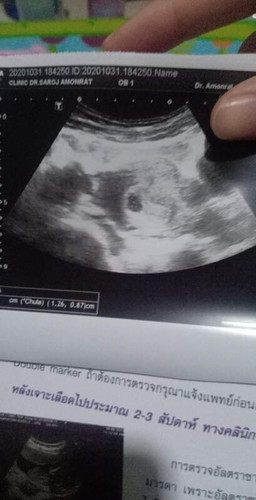

ขอสอบถามหน่อยคะหมอบอกว่าเราว่าท้องได้ประมาน7สัปดาห์แล้ว แต่ยังไม่พบหัวใจเด็ก เราต้องทำใจไหมแบบนี้

ขอสอบถามหน่อยคะหมอบอกว่าเราว่าท้องได้ประมาญ7สัปดาห์แล้ว แต่ยังไม่พบหัวใจเด็ก เราต้องทำใจไหมแบบนี้